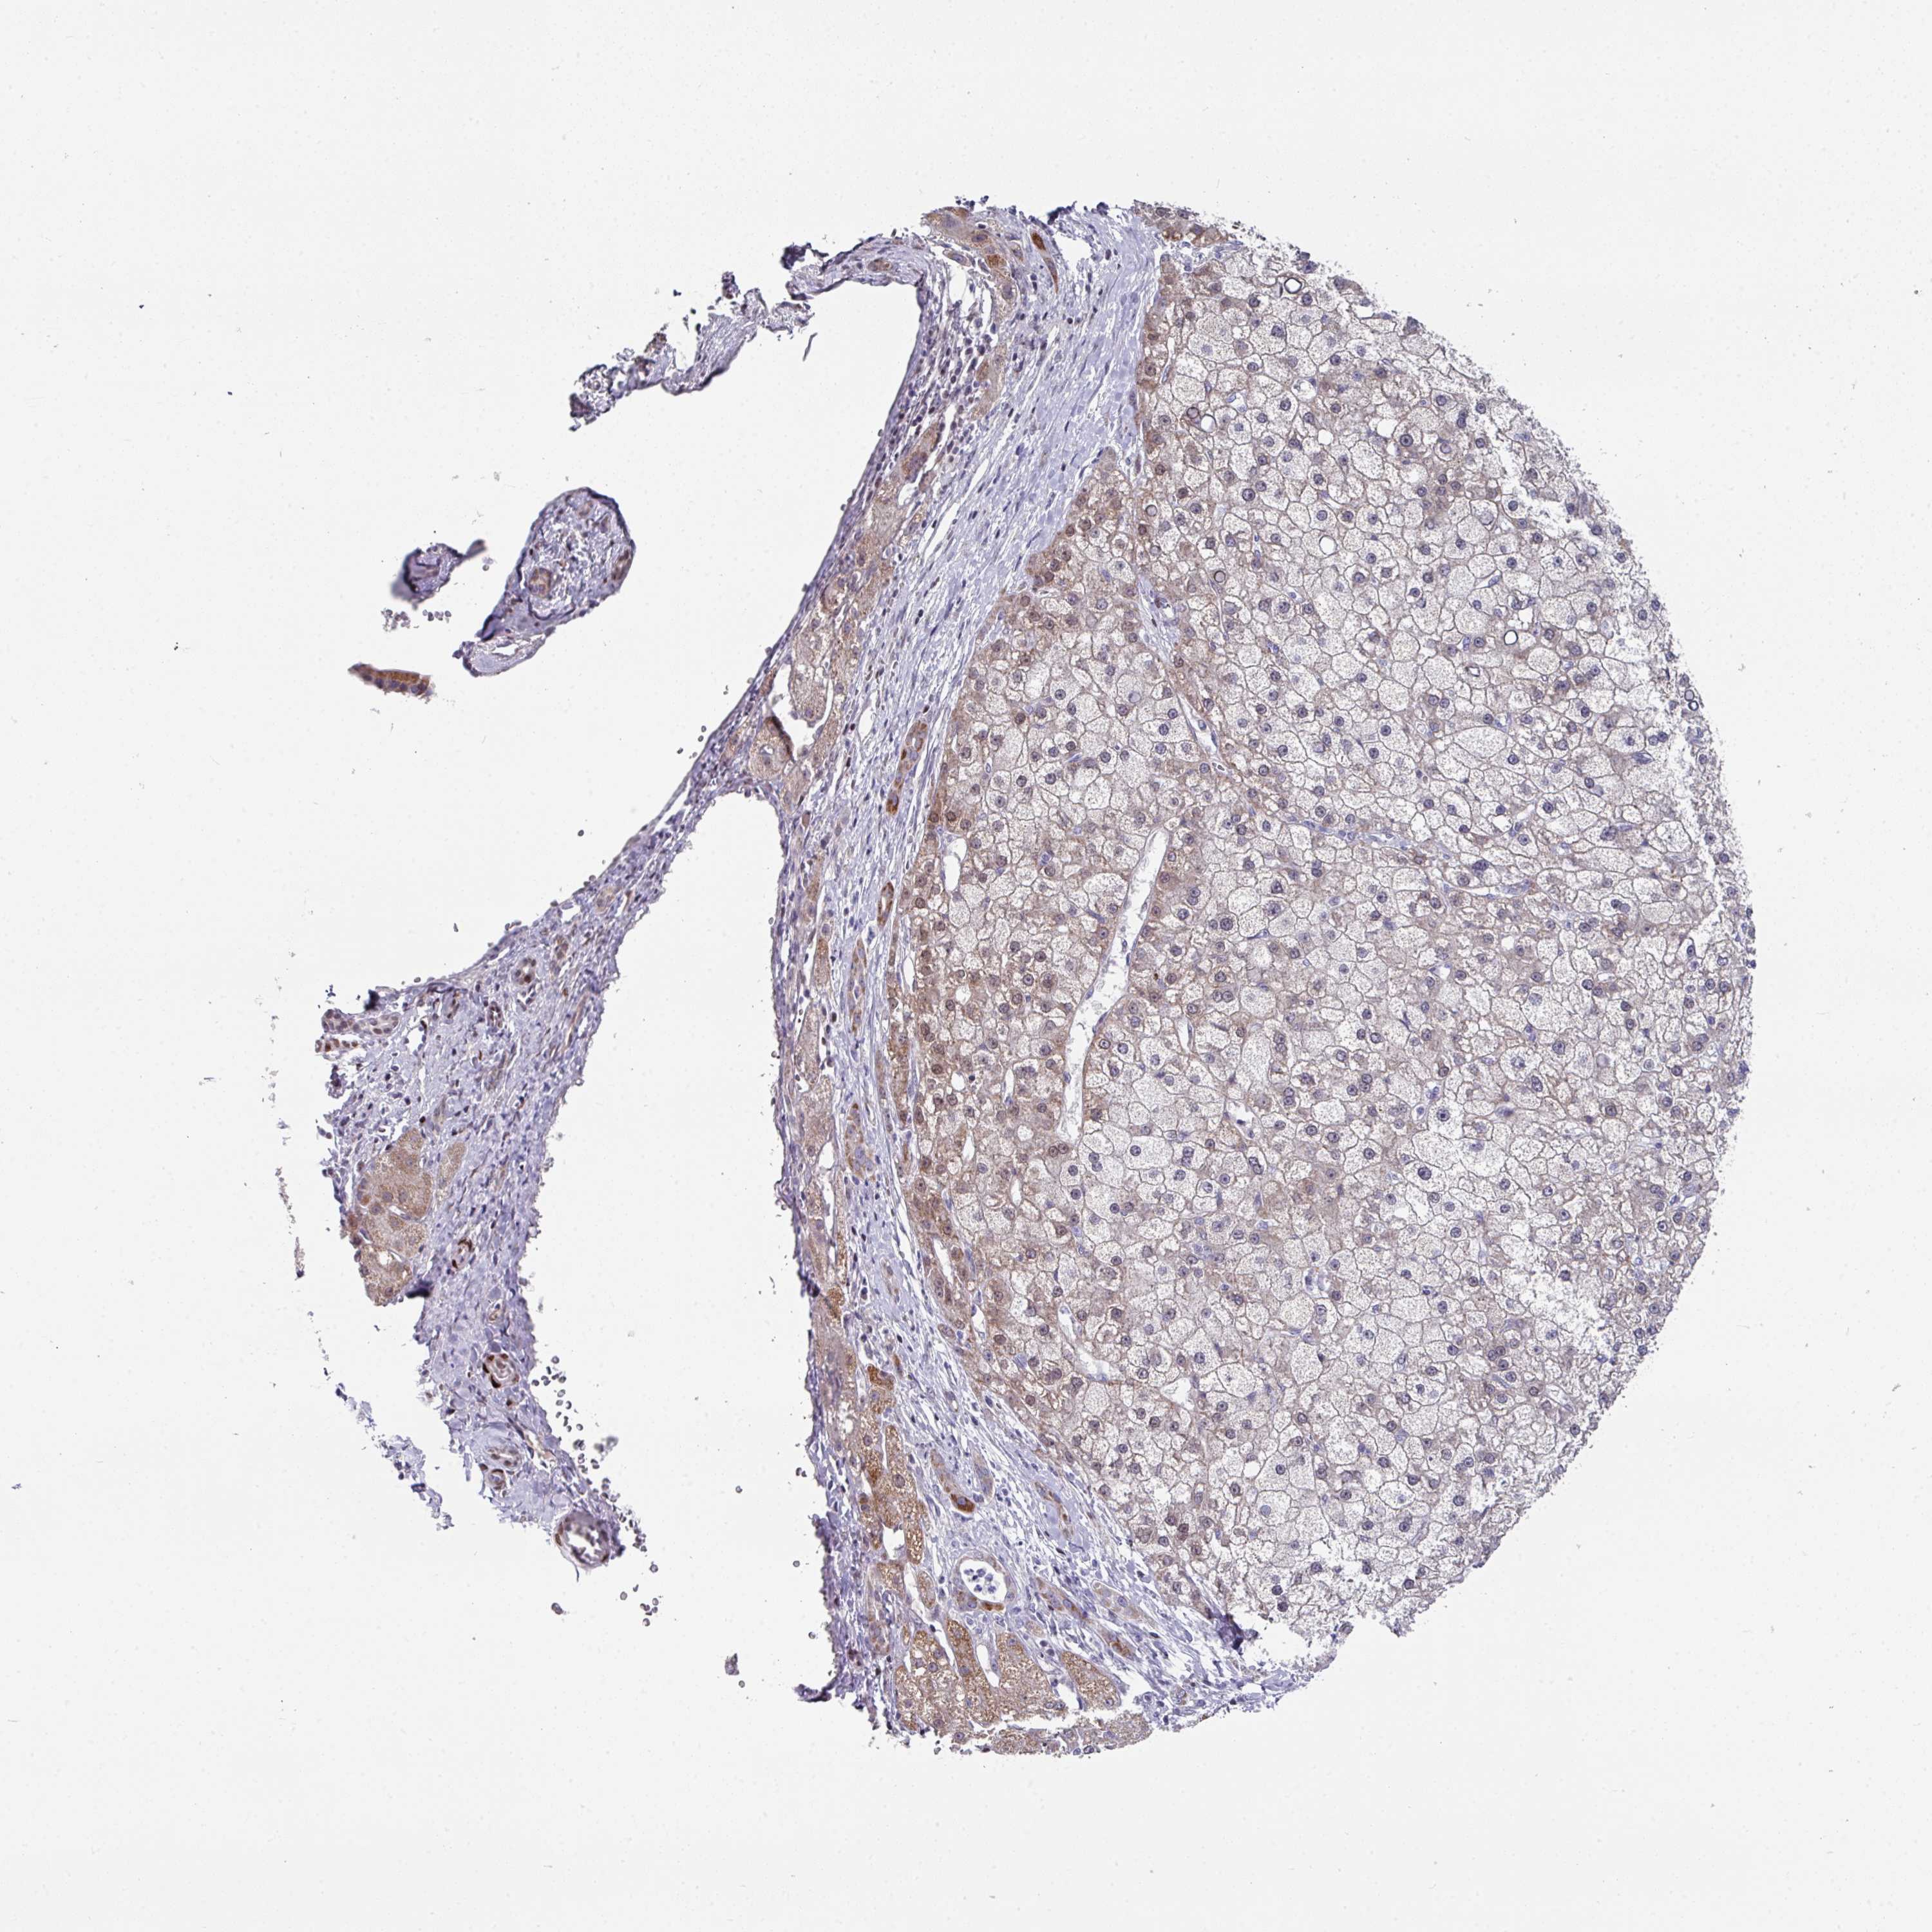

LIVER CANCER - Protein expressioni

A mouse-over function shows sample information and annotation data. Click on an image to view it in a full screen mode. Samples can be filtered based on level of antibody staining by selecting one or several of the following categories: high, medium, low and not detected. The assay and annotation is described here.

Note that samples used for immunohistochemistry by the Human Protein Atlas do not correspond to samples in the TCGA dataset.

Antibody stainingi

Antibody staining in the annotated cell types in the current human tissue is reported as not detected, low, medium, or high, based on conventional immunohistochemistry profiling in selected tissues. This score is based on the combination of the staining intensity and fraction of stained cells.

Each image is clickable and will lead to virtual microscopy that enables deeper exploration of all samples and also displays staining intensity scores, fraction scores and subcellular localization as well as patient and tissue information for each sample.

Antibody HPA048677

Antibody HPA056480

Antibody CAB011574

Staining

High

Medium

Low

Not detected

Intensity

Strong

Moderate

Weak

Negative

Quantity

>75%

75%-25%

<25%

None

Location

Nuclear

Cytoplasmic/membranous

Cytoplasmic/membranous,nuclear

Carcinoma, Hepatocellular, NOS

Cholangiocarcinoma